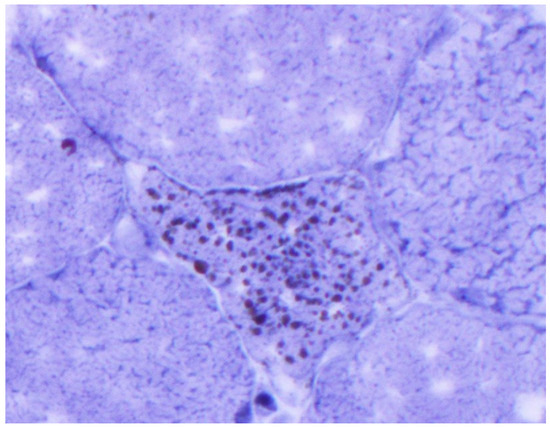

Figure 2.

Immunohistochemistry (CD 68-macrophage) foci of infiltrate.

An 81-year-old woman, with a history of hypertension, dyslipidemia, T12 compression fracture and Alzheimer’s dementia, presented to established care at a geriatric clinic with a chief complaint of two months of gradual progressive symmetric proximal muscle weakness. At baseline, the patient was functionally dependent only on her instrumental activities of daily living. However, her severe weakness resulted in new functional deficits including difficulties in standing, walking and transferring. On medication reconciliation, the patient was noted to be taking atorvastatin 40 mg from two different bottles, doubling her daily dose. Atorvastatin had been started for primary prevention at the age of 79 for an atherosclerotic cardiovascular disease (ASCVD) risk score of >7%. Additional medications at the time of her clinic visit included amlodipine 5 mg daily, donepezil 5 mg nightly, memantine 10 mg twice a day, pantoprazole 40 mg a day and a calcium/Vitamin D supplement. Her exam was significant for 3/5 strength in hip flexors, resulting in the inability to stand unassisted and an inability to abduct her arms past 90 degrees. She was started on prednisone 15 mg orally a day for a presumed diagnosis of polymyalgia rheumatica, and her statin was discontinued. Two weeks later, she was seen in follow-up in the geriatric clinic and found to have profound weakness in the upper and lower extremities as well as new dysphagia and mild dysarthria. She was admitted to the hospital where her workup was notable for mildly elevated troponin-I, elevated AST and ALT and a creatine kinase (CK) of 7630 U/L (normal 38–234 U/L). A urine dipstick showed 3 + blood with only one RBC/high powered field on microscopy. Creatinine was within normal limits. Electromyography (EMG) showed a proximal greater than distal irritable myopathy. A muscle biopsy of the left quadriceps showed segmental necrosis of skeletal muscle fascicles with perivascular infiltration by T-cells, B-cells and plasma cells, and lipid droplet accumulation was consistent with an immune-mediated necrotizing myopathy causing rhabdomyolysis (Figure 1, Figure 2, Figure 3 and Figure 4). Anti-HMG CoA reductase antibodies were positive at >200 units (normal <20 units), whereas ANA, anti-Jo, MI-2, SRP, RNP, Smith, Scl-70 and SS-A/SS-B antibodies all were negative.

The differential for the progressive weakness of proximal muscles in an elderly patient includes both PMR and myopathies. Myopathies can usually be readily differentiated from PMR in that CK is generally elevated. Patients with PMR should not have objective weakness; rather, they typically present with pain limiting their movements [4,5]. In this case, the acute onset and rapid decline of proximal muscle strength in the setting of a markedly elevated CK was most consistent with myopathy. Ultimately, the final diagnosis of statin-induced immune-mediated necrotizing myopathy was cinched by the markedly elevated anti-HMG CoA reductase antibody in combination with characteristic findings on muscle biopsy. Anti-HMG CoA reductase antibodies can be present in the absence of a statin exposure; however, most cases are associated with statin use, particularly those observed in older patients. While the risk of myotoxic side effects of statins have typically been associated with higher potency statins, a dose–response relationship with respect to statin-induced immune-medicated necrotizing myopathy has not been well established [6].